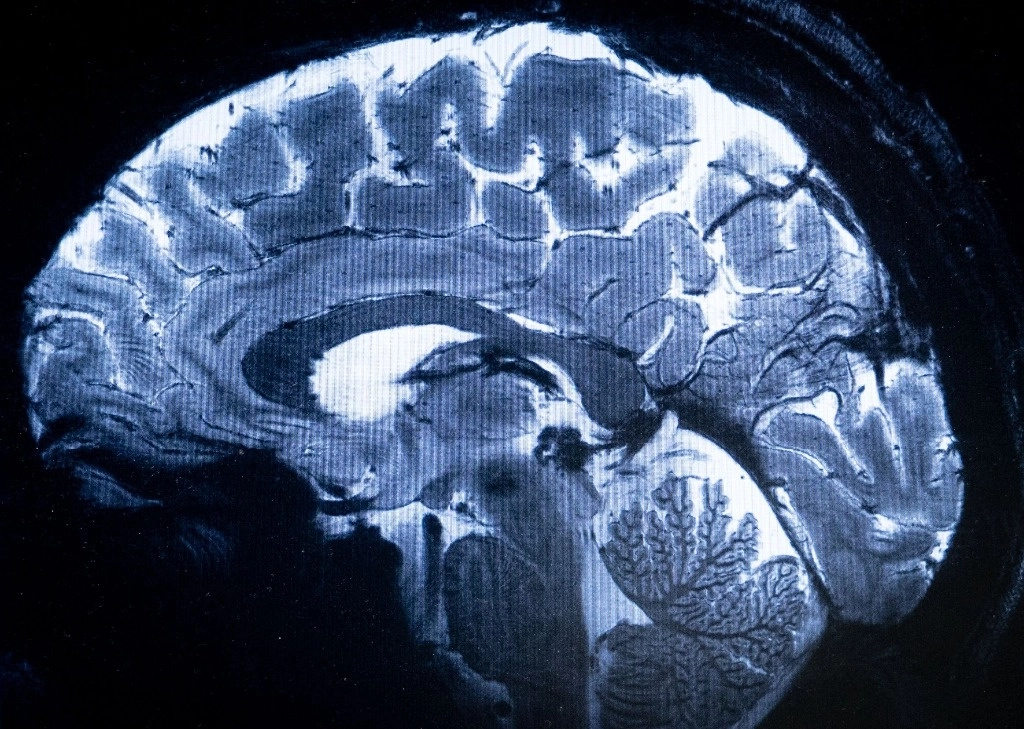

Saclay, 02 de abril del 2024.- El escáner de resonancia magnética (IRM) más potente del mundo ha logrado escanear con un nivel de precisión desconocido el cerebro humano, anunciaron sus responsables en Francia, una proeza que podría ser decisiva para detectar enfermedades.

Esta potencia permite que la máquina escanee imágenes 10 veces más precisas que los IRM comúnmente utilizados en hospitales, cuya potencia normalmente no supera los tres teslas.

En una pantalla de computadora, Vignaud comparó imágenes tomadas por este poderoso escáner, apodado Iseult, con las de un IRM normal.

«Con esta máquina podemos ver los pequeños vasos que alimentan la corteza cerebral, o detalles del cerebelo que eran casi invisibles hasta ahora», dijo.